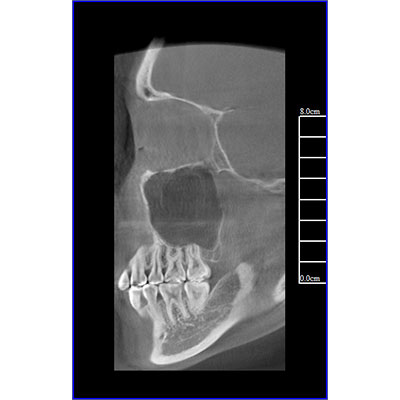

該款牙科CBCT產(chǎn)品采用動(dòng)態(tài)平板探測(cè)器,獲得三維圖像的同時(shí)還具有數(shù)字化全景功能,廣泛應(yīng)用于口腔頜面外科、正畸科、正頜外科、種植科、牙體科、顳下頜關(guān)節(jié)科等術(shù)前術(shù)后。

專有三維重建算法,可提供任意位置高清斷層影像。

通過(guò)三維容積影像,提取高清口腔全景影像。